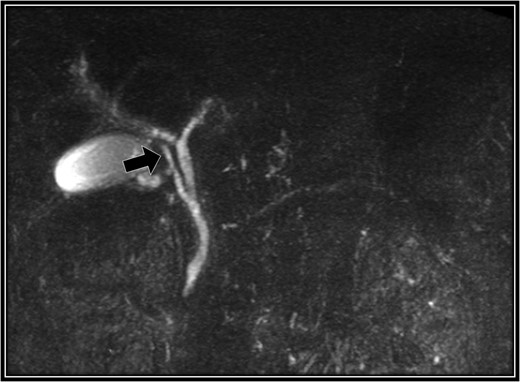

Preoperative magnetic resonance cholangiopancreatography scan. The right accessory hepatic duct branching from the cystic duct (black arrow) dominates an anterior segment of the right hepatic lobe.

A 48-year-old Japanese man experienced abdominal pain after dinner. He underwent computed tomography (CT), and we observed stones in his cystic duct (Fig. 1). Hematological findings showed no liver dysfunction. A magnetic resonance cholangiopancreatography (MRCP) scan demonstrated that the right accessory hepatic duct branching from the cystic duct dominated an anterior segment of the right hepatic lobe (Fig. 2). Therefore, we diagnosed him as cholelithiasis with an anomalous biliary tract, and LC was planned.